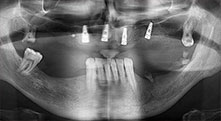

Implantate

Die vier Implantate befinden sich wie geplant in situ. Die distalen Oberkiefermolaren dienen noch zur Fixierung der unterfütterten Prothese, die einen Monat nach Implantation eingegliedert wird.